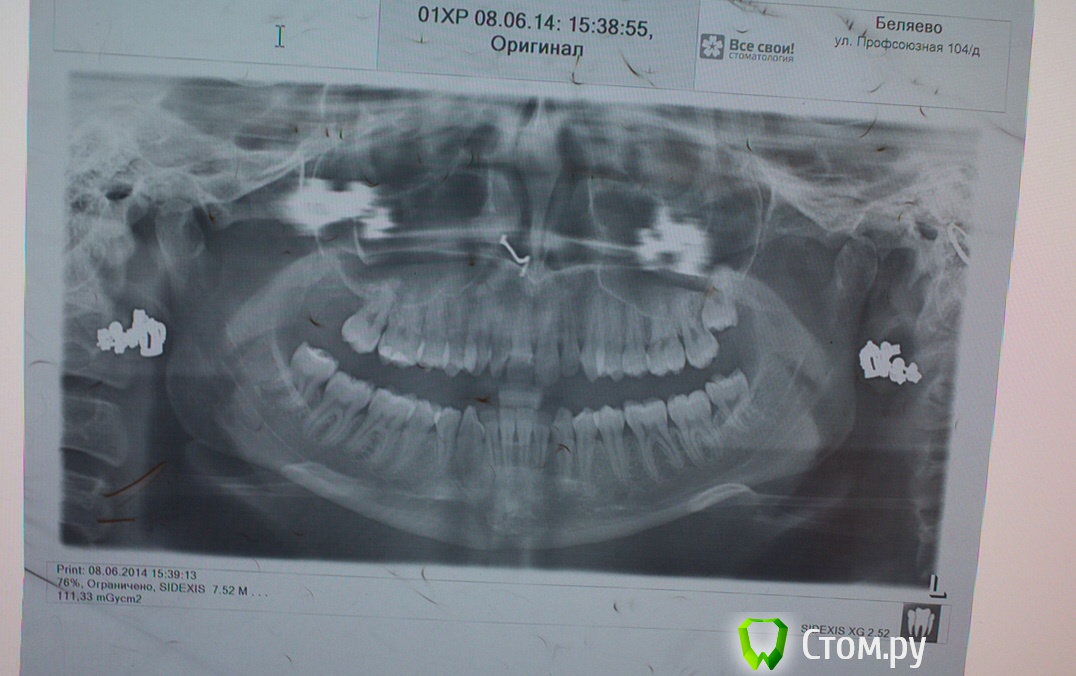

IvanK Опубликовано 13 октября, 2014 Поделиться Опубликовано 13 октября, 2014 Здравствуйте, целью укрепления В данном случае очень важна гигиена и санация полости рта выложите панорамный снимок Ссылка на комментарий

Naga Siren Опубликовано 20 октября, 2014 Автор Поделиться Опубликовано 20 октября, 2014 (изменено) Хорошо, спасибо, я тогда в лс напишу.Прилагаю еще фото Изменено 20 октября, 2014 пользователем Naga Siren Ссылка на комментарий